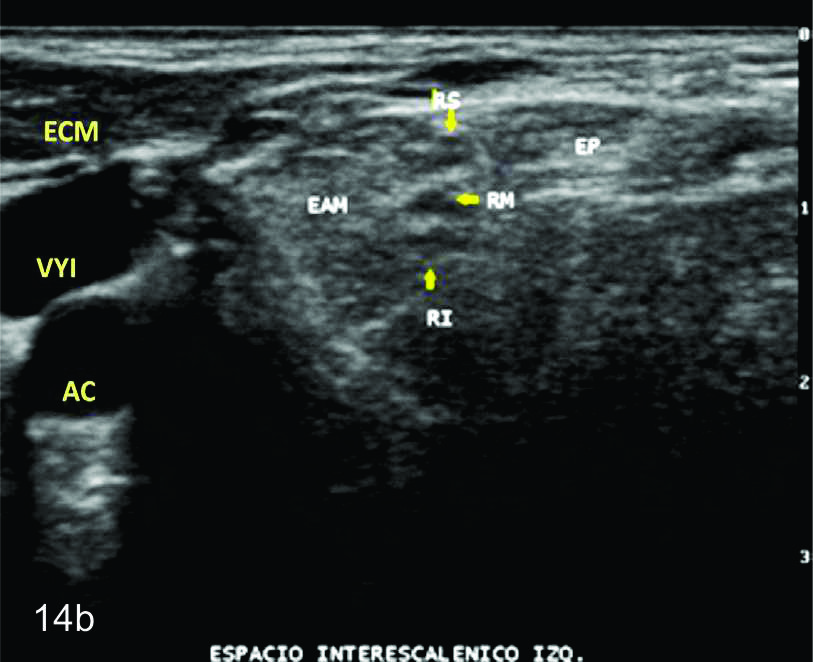

Figura 14 a y b

Lesión traumática del plexo braquial luego de accidente en moto.

A y B- cortes comparativos transversales al plexo braquial al nivel del espacio interescalénico (A-derecho patológico y B-izquierdo sano), se demuestra la asimetría de las estructuras del plexo. RS- tronco superior, RM-tronco medio, RI-tronco inferior, EP- músculo escaleno anterior, EAM-músculos escalenos medio y anterior.